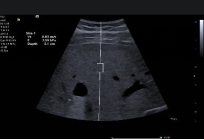

syngo®Arterial Health Package(AHP)动脉健康评估: AHP 为临床提供测量 CIMT,具有高敏感性、非侵入性等优点,测得 CIMT 的诸多参数,并联合患者的其他生理指标(血脂等)预估冠心病、脑卒中的风险指数。